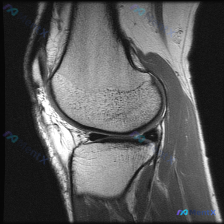

给大家分享一个很有意思的单层面膝关节MRI读片病例,整理一下分析思路,一起聊聊这个矛盾点。 病例影像基础信息 这是一张膝关节矢状位T2加权MRI图像,图像清晰,无明显运动伪影,可清晰识别股骨远端、胫骨近端、髌骨、半月板、髌上囊等关键解剖结构: - 骨骼:骨皮质连续,未见明确骨折线,骨髓信号无异常局灶...

刚整理了一份单一切面膝关节MRI的读片分析,针对问题「半月板异常」做了完整思路梳理,分享给大家一起讨论。 病例影像基础信息 这是一张膝关节MRI T2加权矢状位图像,仅提供这一个切面,我们先整理已经观察到的客观征象: 1. 序列与解剖:T2加权矢状位,显示膝关节内侧/中间切面,可见髌骨、股骨远端、胫...

病例资料整理 这是一份单张膝关节MRI矢状位T2序列(疑脂肪抑制)的影像分析病例,临床核心疑问是排查半月板异常,整理信息如下: 基本影像信息 影像类型:膝关节MRI T2加权矢状位(单张) 影像观察结果 1. 骨骼与软骨:股骨、胫骨骨皮质连续,髓腔信号均匀,无明显骨髓水肿;股骨髁、胫骨平台关节软骨边...